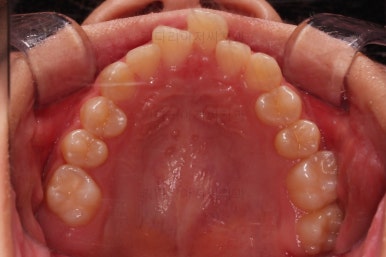

1. 초진

초진 시 입안의 모습입니다.

눈에 띄는 부분은 당연히 앞니가 삐뚤고, 앞니 하나가 앞으로 튀어나온 모습인데요.

자세히 관찰해 보면 다른 문제점들이 보입니다.

우선 위아래 앞니가 깊숙히 맞물려 있는 과개교합 양상인데요.

✅ 앵글씨 2급 부정교합

이번 환자분은 어금니가 위아래가 지그재그 서로 엇갈려 꽉 끼이는 교합이 아니라 1대1로 치아가 부딪혀 있는 상태였습니다.

✅ 악궁 확장

악궁확장 내용이 나올 때면 매번 말씀 드리는 내용이 있습니다.

치열이 삐뚤었다고 공간확보 목적으로 악궁확장을 하는 건 아니다.

아래와 위의 턱뼈의 크기 부조화가 있을 때 위턱을 넓혀주는 것이 악궁확장이며, 저희 부산청소년교정치과 키다리아저씨치과에서는 정교한 3차원 CT분석을 이용해서 골격의 크기를 비교해서 꼭 필요한 경우에 악궁확장을 해주게 됩니다.

당연히 확장을 하면 부가적으로 공간확보가 일정 부분 더 잘된다는 효과도 있지만 공간확보를 위해서 턱뼈의 크기가 조화로운데도 불구하고 악궁확장을 한다면 또 다른 좋지 못한 결과가 생길 수 있어서 매우 조심스러운 평가가 선행되어야 합니다.

이번 환자분은 악궁확장이 필요한 케이스였으며, 청소년이었기 때문에 별도의 미니스크류 없이 일반 확장장치를 이용했습니다.